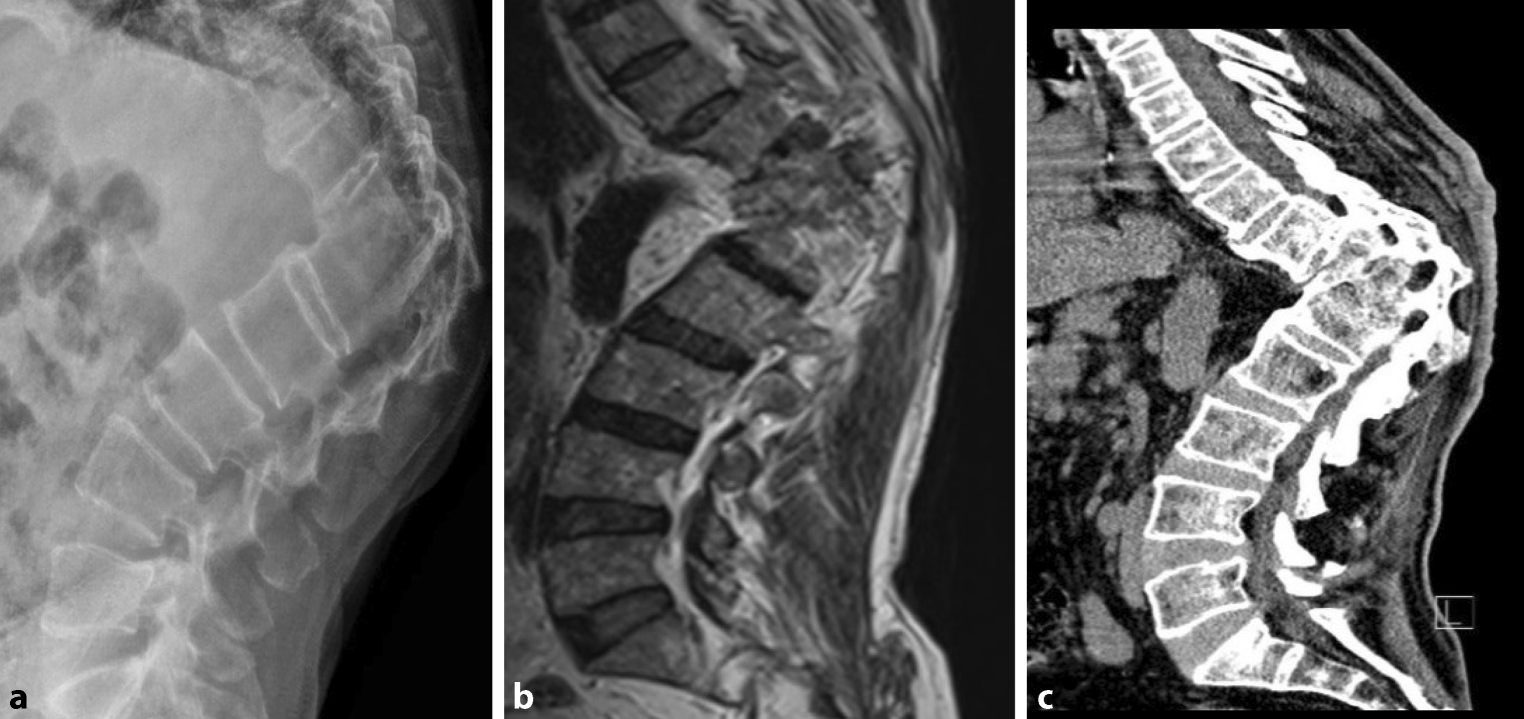

Fig. 5

This 69-year-old male patient in 2020 was in inpatient care with a fracture of vertebral bodies due to tuberculosis infection. A 90° gibbus in the area of the thoracolumbar transition TH12–L1 with ankylosis and a Cobb angle of 45° is visible. a Conventional X‑ray. b Magnetic resonance imaging. c Conventional computed tomography